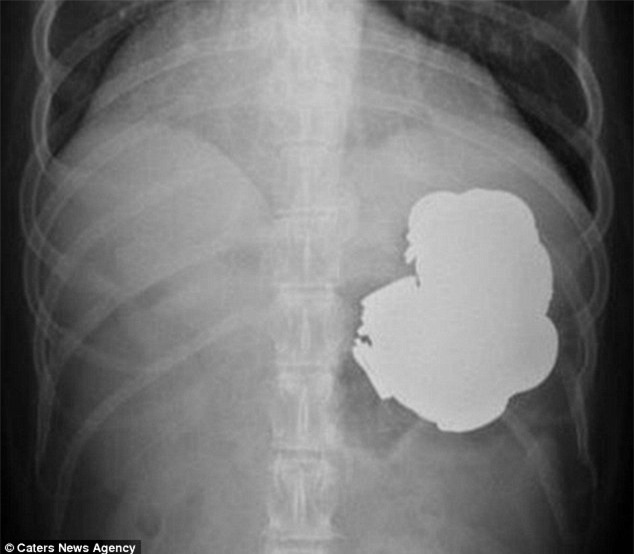

Nhưng họ đã phải tròn mắt kinh ngạc khi phẫu thuật và phát hiện ra trong bụng của bệnh nhân có 140 đồng xu, 150 cái đinh, một ít bu lông, ốc vít, pin, thậm chí cả nam châm.

Singh nói rằng, ông không nghĩ rằng mình bị đau dạ dày là do ăn kim loại. Các bác sĩ đã thực hiện 240 ca phẫu thuật nội soi để loại bỏ dị vật nhưng không hết. Một nhóm 5 bác sĩ cũng thực hiện đại phẫu suốt 9 giờ đồng hồ mà vẫn không thể xong việc.